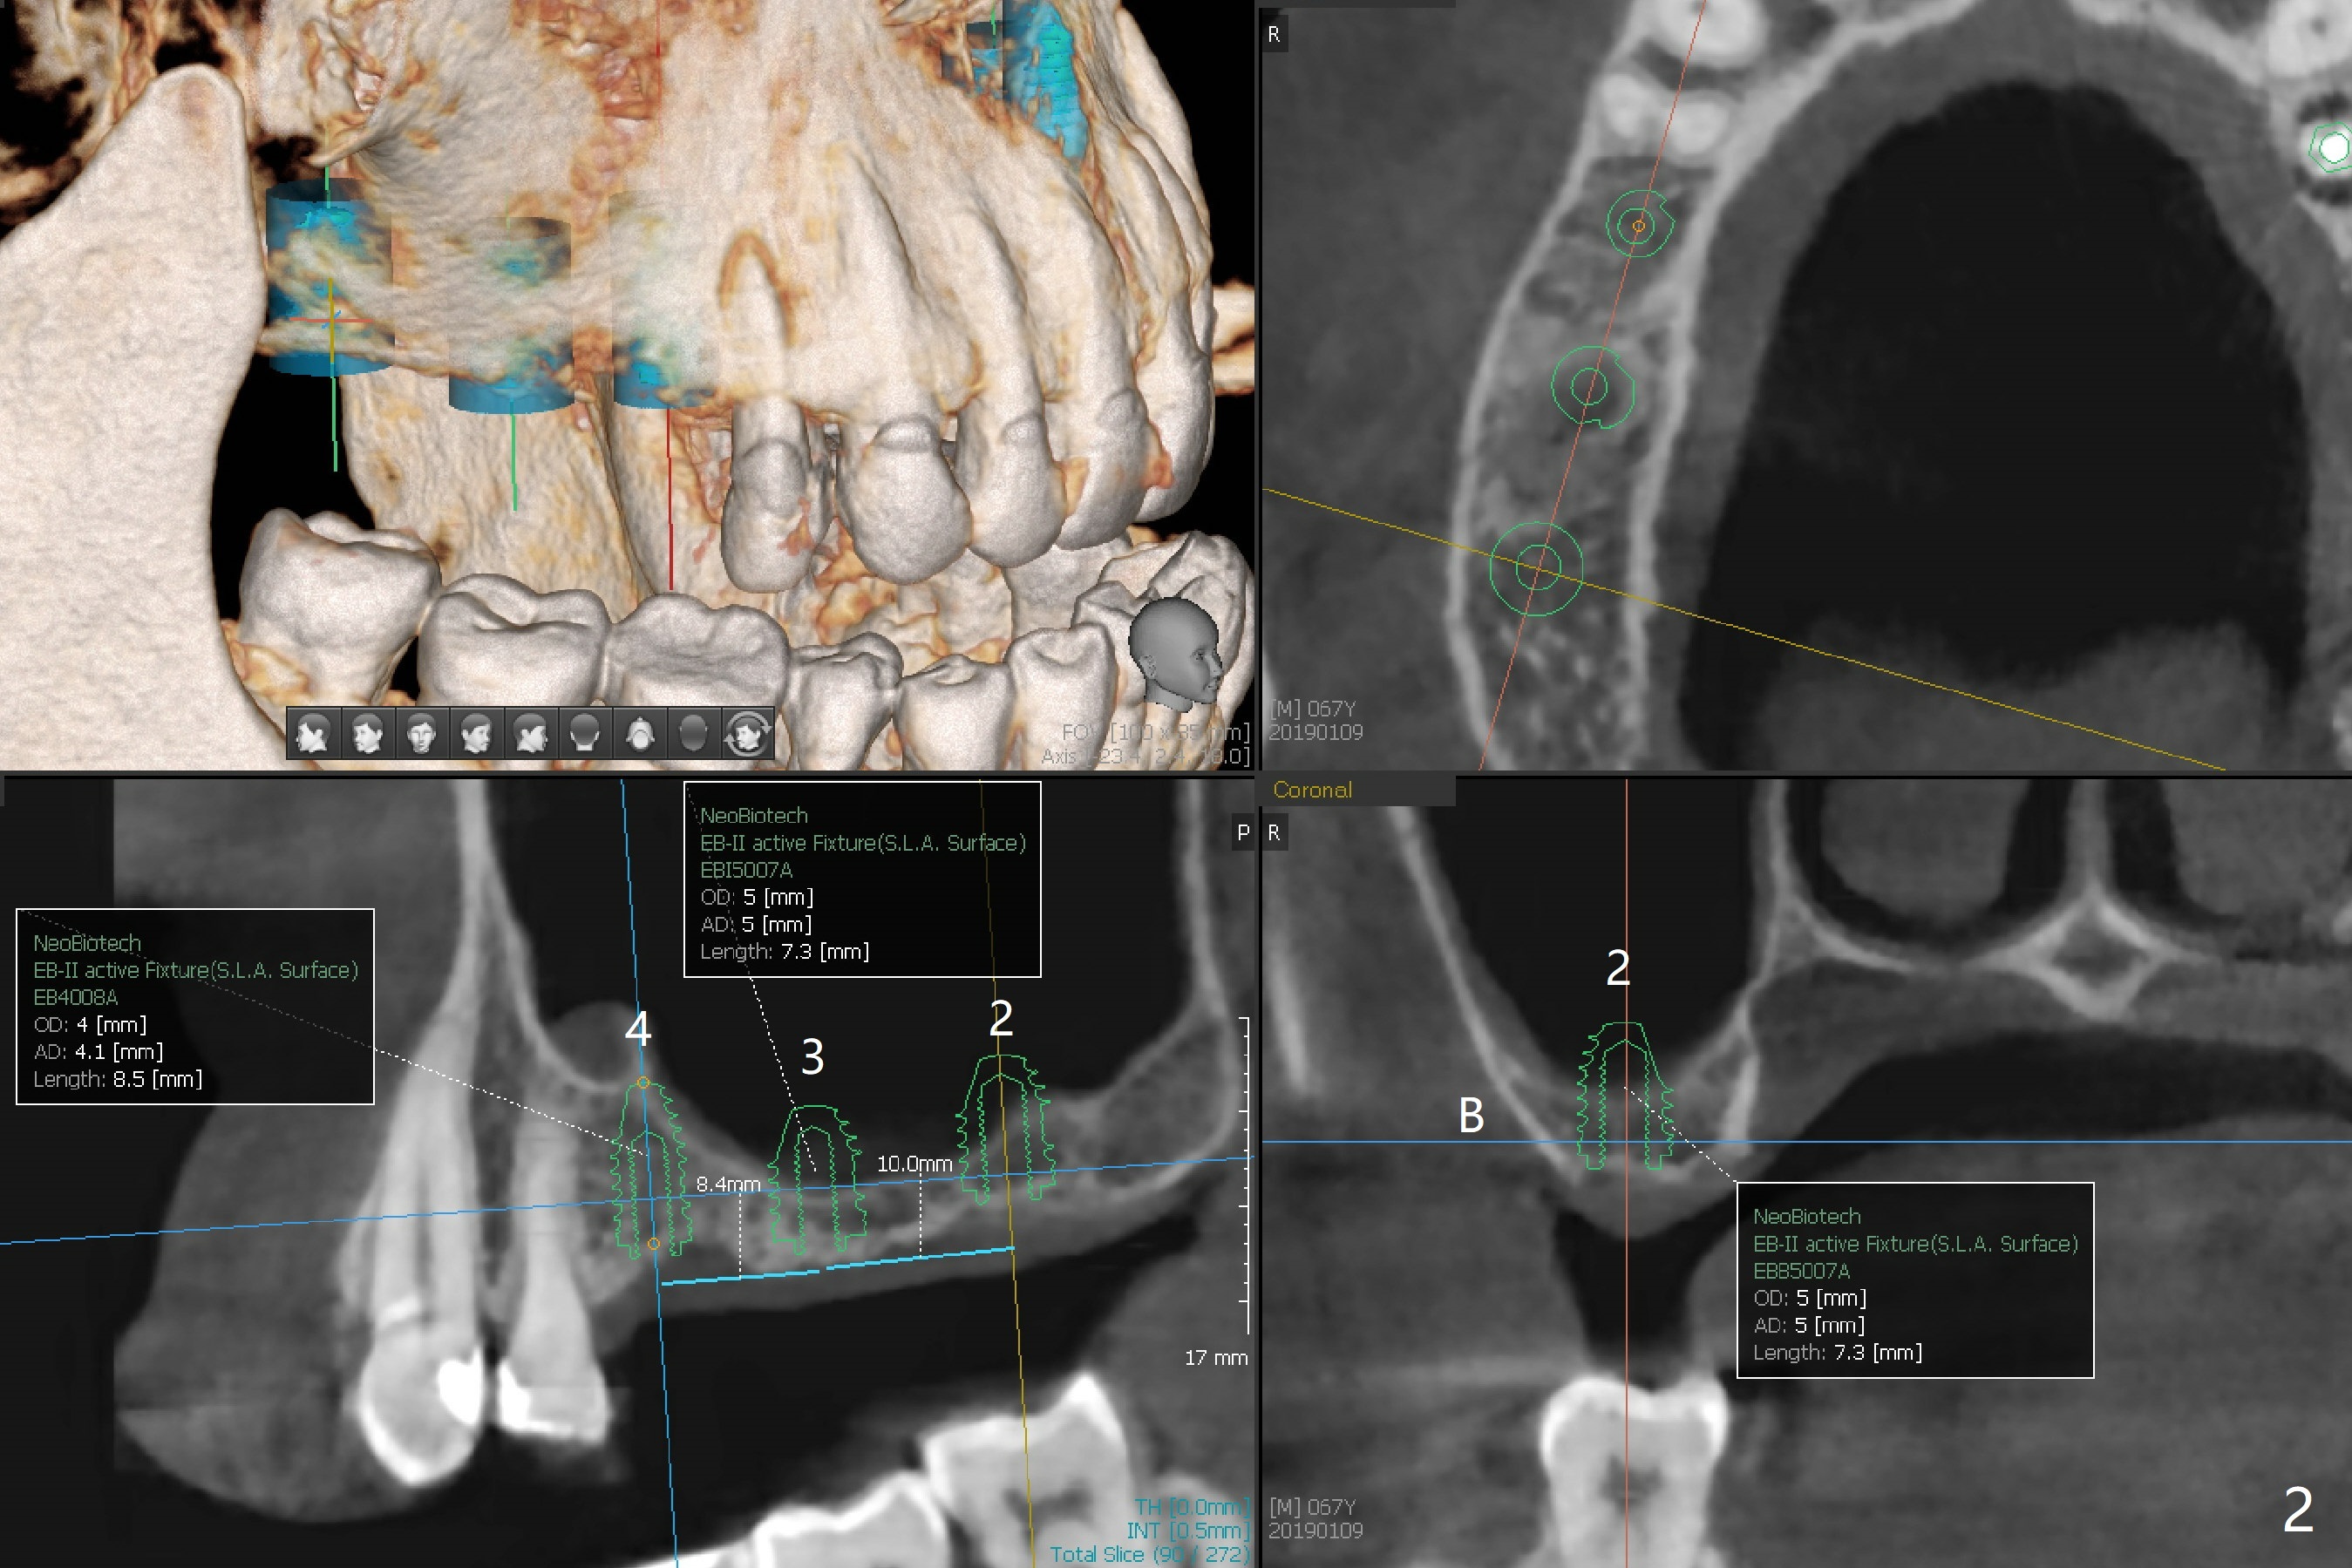

A 63-year-old woman wants to change upper RPD (for #2-4, 13 and 14) to implants because of denture-associated candidiasis. She is afraid of osteoporosis, although the implant at #18 is doing fine almost 3 months post cementation (Fig.1). One way to restore the upper right quadrant is to place 3 short implants (7.3 or 8.5 mm) with guide with simultaneous internal or external sinus lift (Fig.2-4). The tooth #12 appears to have root fracture with periradicular radiolucency (Fig.5); an immediate implant will be placed. While a short implant will be placed at #13, no implant will be placed at #14 because of 1 mm bone (Fig.6). A cantilever FPD will be fabricated in the upper left quadrant. The thick left sinus membrane is a problem as related to a lift?